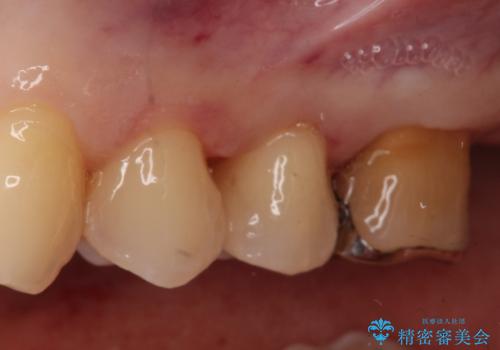

- 左上の4番目と5番目の歯(小臼歯)に入っている銀歯を白くしたいという主訴でご来院されました。

診査の結果、長年使用されていたメタルインレーは経年劣化により適合が悪くなっており、金属の溶け出しによる歯肉の変色や、内部での虫歯再発のリスクも懸念される状態でした。そこで、金属を一切使用しないメタルフリー治療として、耐久性と審美性に優れたセラミックインレーへのやりかえをご提案しました。

治療ではまず、古いメタルインレーを慎重に除去し、内部のわずかな虫歯を取り除いてから形を整えました。

装着したセラミックインレーは、隣り合う天然歯と見分けがつかないほど自然な色調と透明感を再現しています。また、セラミックはプラーク(歯垢)が付着しにくく、適合性が非常に高いため、二次的な虫歯の予防にも大きく貢献します。

お口を開けた際に目立っていた銀色の部分が解消され、清潔感のある明るい口元になりました。金属アレルギーの心配もなく、健康的で美しい状態を長期的に維持することが可能です。